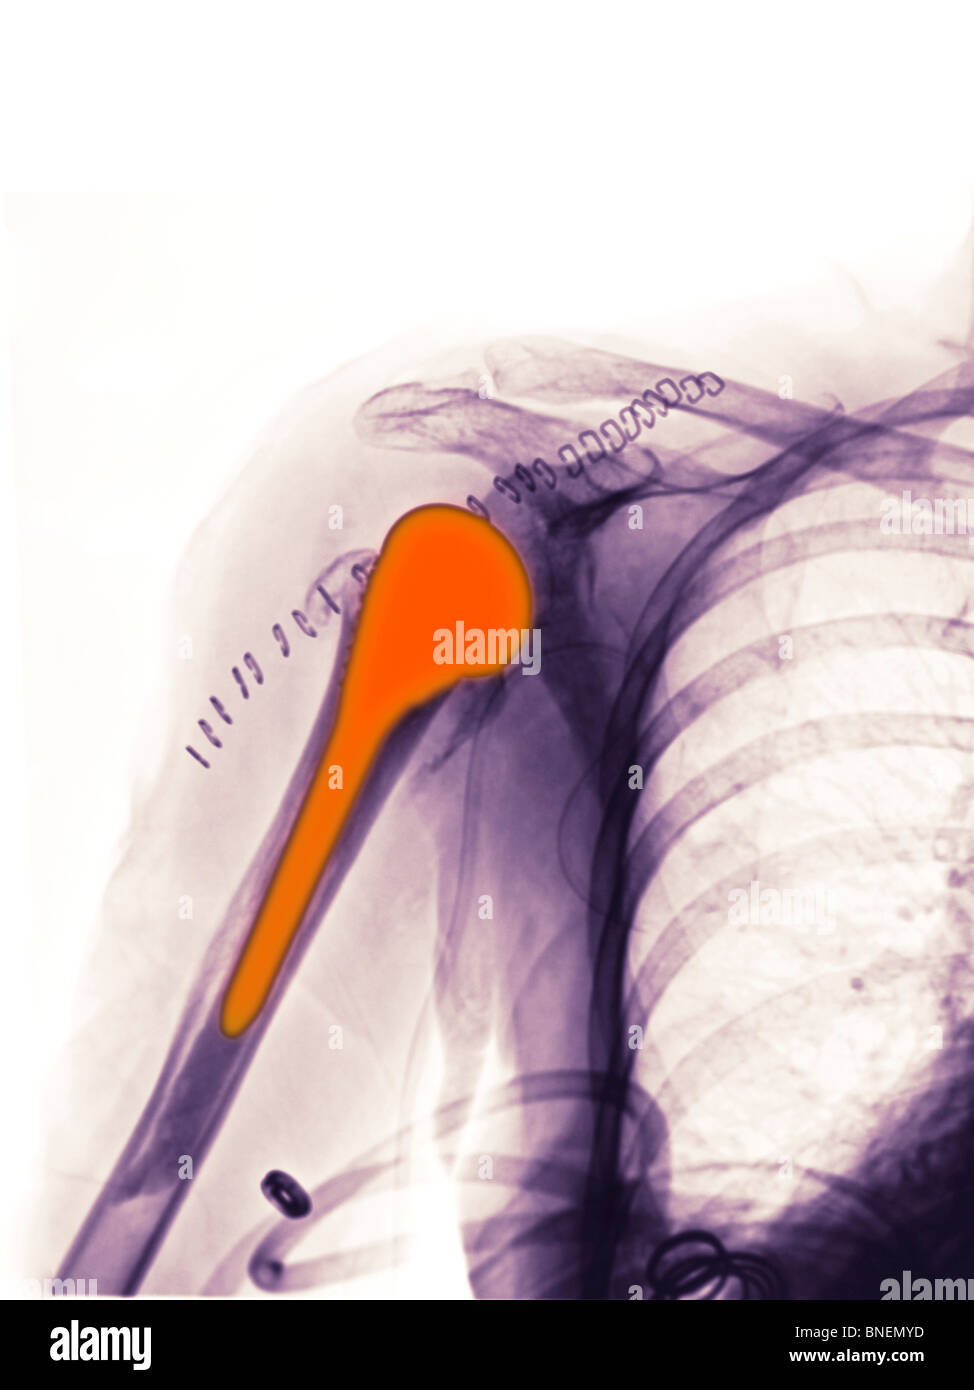

From www.alamy.com

xray showing shoulder replacement Stock Photo Alamy Shoulder Replacement X Rays This article is chiefly limited to the routine radiographic evaluation of shoulder arthroplasties and guidelines to. They can show loss of the normal joint space between bones, flattening or irregularity in the shape of the bone, bone spurs, and loose pieces of cartilage or bone that may be floating inside the joint. Reverse shoulder arthroplasty, total shoulder. shoulder arthroplasties. Shoulder Replacement X Rays.